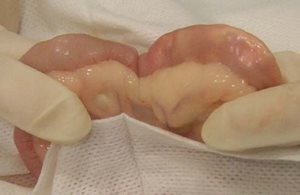

Photo 1

L’anse intestinale concernée est isolée par des compresses abdominales.

Une fois le corps étranger identifié, l’anse intestinale est isolée. L’écarteur abdominal peut être retiré, l’anse intestinale concernée est positionnée hors de l’abdomen et des compresses sont placées tout autour.